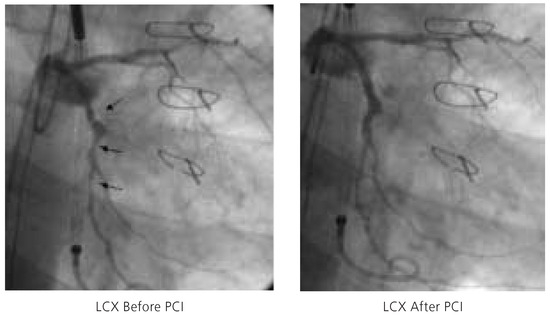

Figure 5.

Three complex, high-grade stenoses of the circumflex artery (LCX) before (left) and after (right) percutaneous coronary intervention. PCI = percutaneous coronary intervention.

Following this, the left femoral artery was punctured and a 5F Amplatz guiding catheter (Cordis, Johnson and Johnson, Miami, USA) used to selectively intubate the left main coronary ostium. Percutaneous coronary intervention of the left circumflex artery was performed by means of balloon pre-dilation, followed by insertion of a Cypher™ (Cordis, Johnson and Johnson, Miami, USA) stent (fig. 5). During the intervention no significant haemodynamic changes were noted, and the patient tolerated the balloon inflations well. At the end of the percutaneous coronary intervention, the Impella Recover® LP 2.5 system was withdrawn and haemostasis was ensured by manual compression for 30 minutes. Blood loss was estimated of less than 100 ml during the intervention. The periprocedural measurement of cardiac biomarkers was unrevealing and there were no electrocardiographic changes. The patient was ambulated after 6 hours and there were no peripheral access complications. He was discharged home on the second day and will be readmitted for implantation of an implantable cardioverter defibrillator in one week.